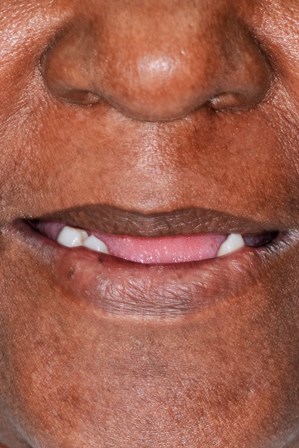

After